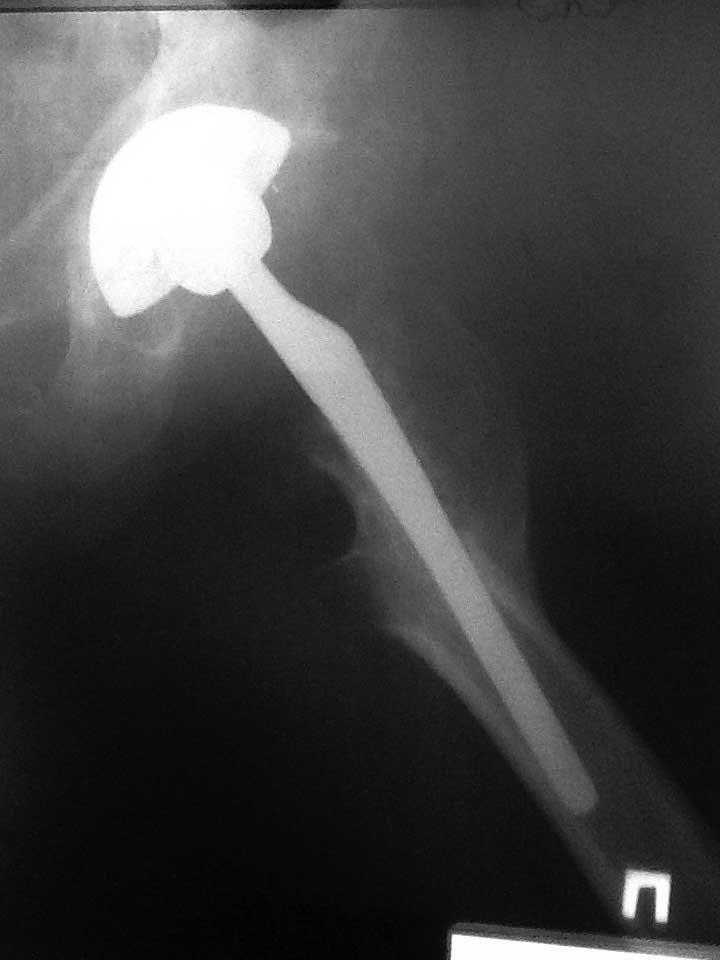

Пациент 60-ти  лет около двух лет назад выполнено тотальное б/цементное эндопротезирование по поводу двухстроннего коксартроза, состояния после остеотомий проксимальных отделов бедренных костей. Послеоперационный период спокойный. Больной появлялся на контрольные осмотры в 2, 6, 12 мес, 2 года.  На протяжении всего времени отмечает выраженный болевой синдром в области оперированного бедра, передвигается при помощи костылей. Обследован у невролога, уровень С реактивного протеина и лейкоформула в пределах нормы, отечности на бедре нет. Учитывая измененный проксимальный отдел бедра и как следствие интраоперационные трудности обращает на себя внимание передне-заднее расположение ножки эндопротеза (конфликт с задним кортикалом) Может ли такое положение компонента быть причиной болевого синдрома? Поможет ли ревизионное вмешательство по удалению ножки и корректная установка компонента?